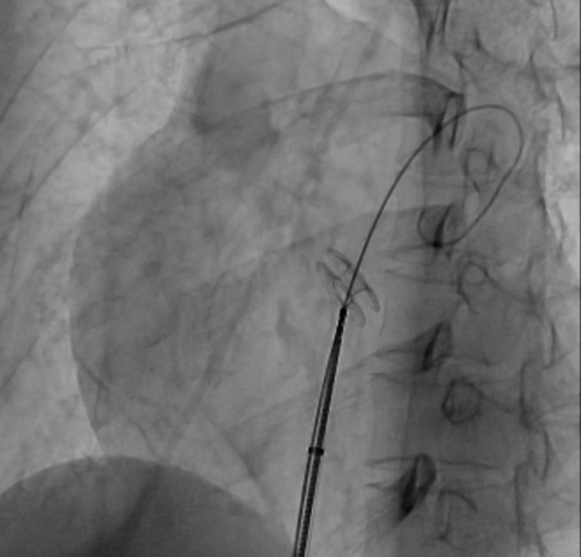

在局麻下为患者行右心导管检查,测量左房压16/8(11) mmHg ,右房压23/11(15) mmHg,肺动脉压167/93(116)mmHg,左右房压差为4 mmHg,全肺阻力 1605 dyn·s·cm-5, 肺血管阻力 1453 dyn·s·cm-5,心输出量 5.6 L/min,心指数 3.7 L/min/m2 ,不吸氧的情况下SPO2 92%,经胸超声定位后行房间隔穿刺,送入预塑形的左房导丝建立轨道,选择6mm外周动脉高压球囊对房间隔进行谨慎扩张三次,送入10F输送系统,体外排气充分后送入心房分流器(WKASD 20-6mm)至房间隔处支撑开此前球囊撕开的不规则房间隔造口,透视及超声观察分流器形态位置良好,释放封堵器。

球囊房间隔造口术